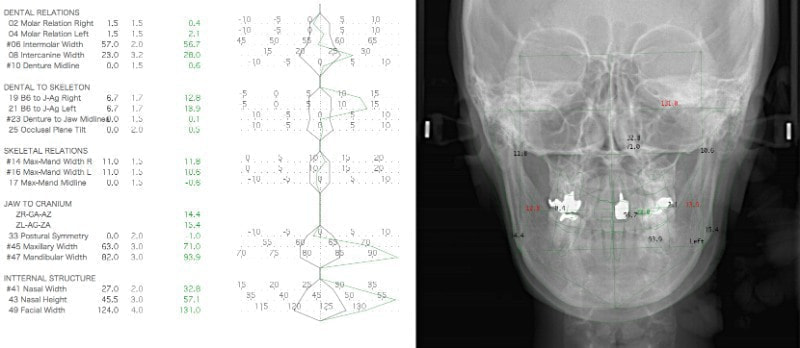

セファロ分析正貌

顔面の幅径はかなり狭い傾向にあります。